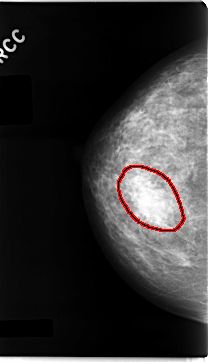

C_0060_1.RIGHT_CC

FILE: C_0060_1.RIGHT_CC.OVERLAY

TOTAL_ABNORMALITIES 1

ABNORMALITY 1

LESION_TYPE MASS SHAPE OVAL MARGINS CIRCUMSCRIBED

ASSESSMENT 3

SUBTLETY 5

PATHOLOGY BENIGN

TOTAL_OUTLINES 1

BOUNDARY